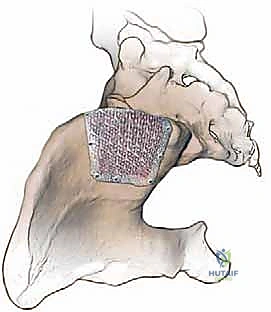

يمكن للجراح أخذ الطعم العظمي من جزأين رئيسيين في الحرقفة، ويتم اختيار الموقع بناءً على وضعية المريض أثناء الجراحة (على بطنه أم على ظهره) ونوع وكمية العظم المطلوب:

1. التشريح الأمامي لحرقفة الحوض (Anterior Iliac Crest)

يُفضل استخدام الجزء الأمامي عندما يكون المريض مستلقياً على ظهره (Supine)، وغالباً ما يُستخدم للحصول على طعم عظمي هيكلي ثلاثي القشرة (Tricortical Structural Graft)، والذي يُستخدم بكثرة في دمج الفقرات العنقية من الأمام، أو في جراحات الوجه والفكين، أو الحالات التي تتطلب دعامة هيكلية قوية لا تتحمل وزناً هائلاً.

- المعالم العظمية الرئيسية: النقطة البارزة والأكثر وضوحاً في هذه المنطقة هي الشوكة الحرقفية الأمامية العلوية (ASIS). على بعد حوالي 2 إلى 3 سنتيمترات خلف هذه الشوكة، يوجد بروز يُسمى الحديبة الحرقفية (Iliac Tubercle). هذه الحديبة هي الجزء الأكثر سمكاً واتساعاً في الحرقفة الأمامية، وتُعد الهدف الأساسي والآمن لأخذ الطعم العظمي الهيكلي.

- المخاطر العصبية والوعائية الدقيقة: الجراحة في هذه المنطقة تتطلب معرفة دقيقة بمسار الأعصاب لتجنب إصابتها:

- العصب الجلدي الفخذي الوحشي (Lateral Femoral Cutaneous Nerve - LFCN): هذا العصب مسؤول عن الإحساس في الجزء الخارجي من الفخذ. يمر عادةً في الناحية الداخلية (الإنسية) للشوكة الحرقفية الأمامية العلوية. ومع ذلك، في بعض المرضى، قد يختلف مساره ويمر فوق الشوكة أو في الناحية الخارجية (الوحشية). إذا تعرض هذا العصب للإصابة أو التمدد أثناء الجراحة، فقد يُصاب المريض بحالة مزعجة تُعرف باسم ألم الفخذ المذلي (Meralgia Paresthetica)، والتي تتميز بشعور بالخدر، الوخز، أو ألم حارق يشبه الكهرباء على طول الجزء الخارجي من الفخذ.

- العصب الحرقفي الإربي (Ilioinguinal Nerve) والعصب الحرقفي الخثلي (Iliohypogastric Nerve): هذه الأعصاب تمر عبر عضلات جدار البطن. عند سحب عضلات البطن بقوة للوصول إلى الحافة الداخلية للحوض، قد تتعرض هذه الأعصاب للضغط، مما يسبب ألماً ينتشر نحو منطقة الفخذ الداخلية والأعضاء التناسلية.

- العضلات الملتصقة: منطقة الحرقفة الأمامية هي نقطة ارتكاز للعديد من العضلات الهامة. من الخارج تنشأ العضلة الموترة للفافة العريضة (Tensor Fascia Latae) والعضلات الألوية (Gluteus muscles). ومن الداخل تلتصق العضلة الحرقفية (Iliacus). يجب فصل هذه العضلات بحذر شديد لتقليل النزيف والألم بعد العملية.